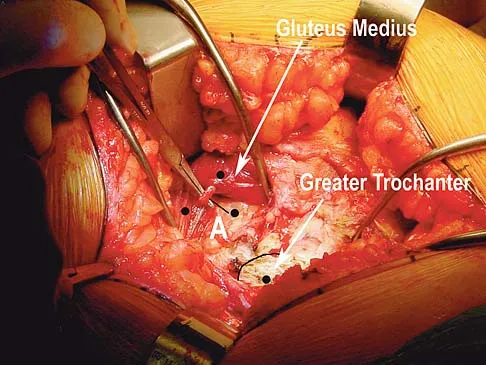

Question 73

A direct lateral (Hardinge) approach is used during total hip arthroplasty. The structure labeled A in Figure 7 is the

Explanation